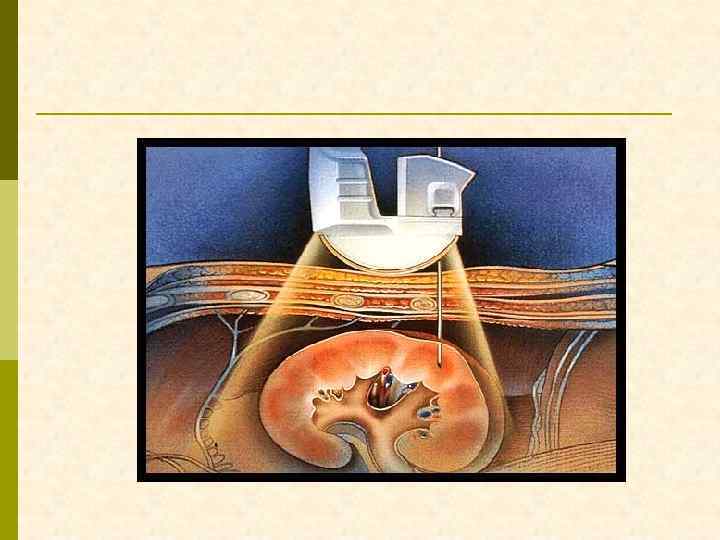

ЛОКАЛИЗАЦИЯ БИОПСИОННОЙ ИГЛЫ ПРИ УЛЬТРАЗВУКОВОМ ИССЛЕДОВАНИИ